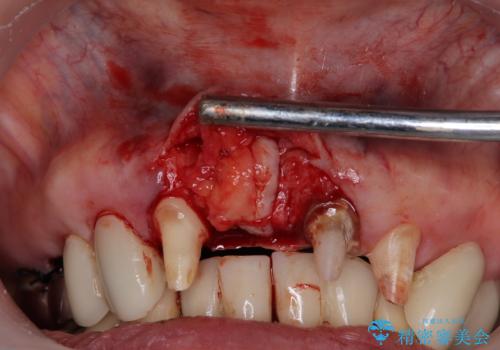

前歯のインプラントは埋入されたポジションが望ましい位置ではなく、インプラントを活用して段差を回収することは不可能と判断し、歯肉移植によりインプラントを隠して、ブリッジにて歯肉ラインを整えることとしました。

- 外科手術のため、術後に出血、痛みや腫れ、違和感を伴います